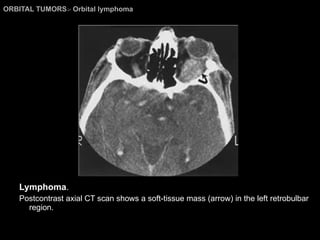

Orbital Lymphoma The CT and MR imaging findings; Usually nonspecific:  impossible to differentiate from  orbital pseudotumors, lacrimal gland tumors, optic nerve tumors, Graves’ orbitopathy, primary orbital tumors, or orbital cellulitis. Homogeneous masses of relatively high density and sharp margins. More often seen in the anterior portion, the retrobulbar area, or in the superior orbital compartment.  Mild to moderate enhancement.

ORBITAL TUMORS >  Orbital lymphoma Lymphoma . Postcontrast axial CT scan shows a soft-tissue mass (arrow) in the left retrobulbar region.